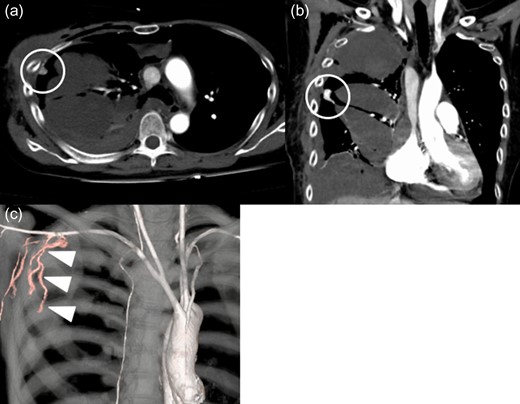

Contrast-enhanced computed tomography findings at 1 week. There is a tuberous enhancement in the right chest cavity near the fourth intercostal space (circle). Right lateral thoracic artery (arrow heads) connect to a tuberous enhancement. Axial view (a). Coronal view (b). Three-dimensional volume rendering computed tomography (c).